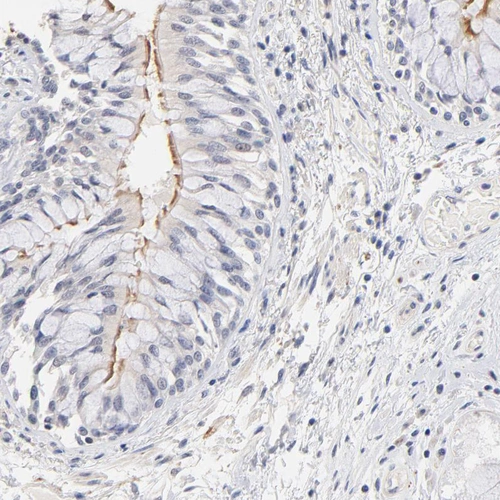

Immunohistochemical staining of human fallopian tube shows moderate to strong positivity in cilia in glandular cells.